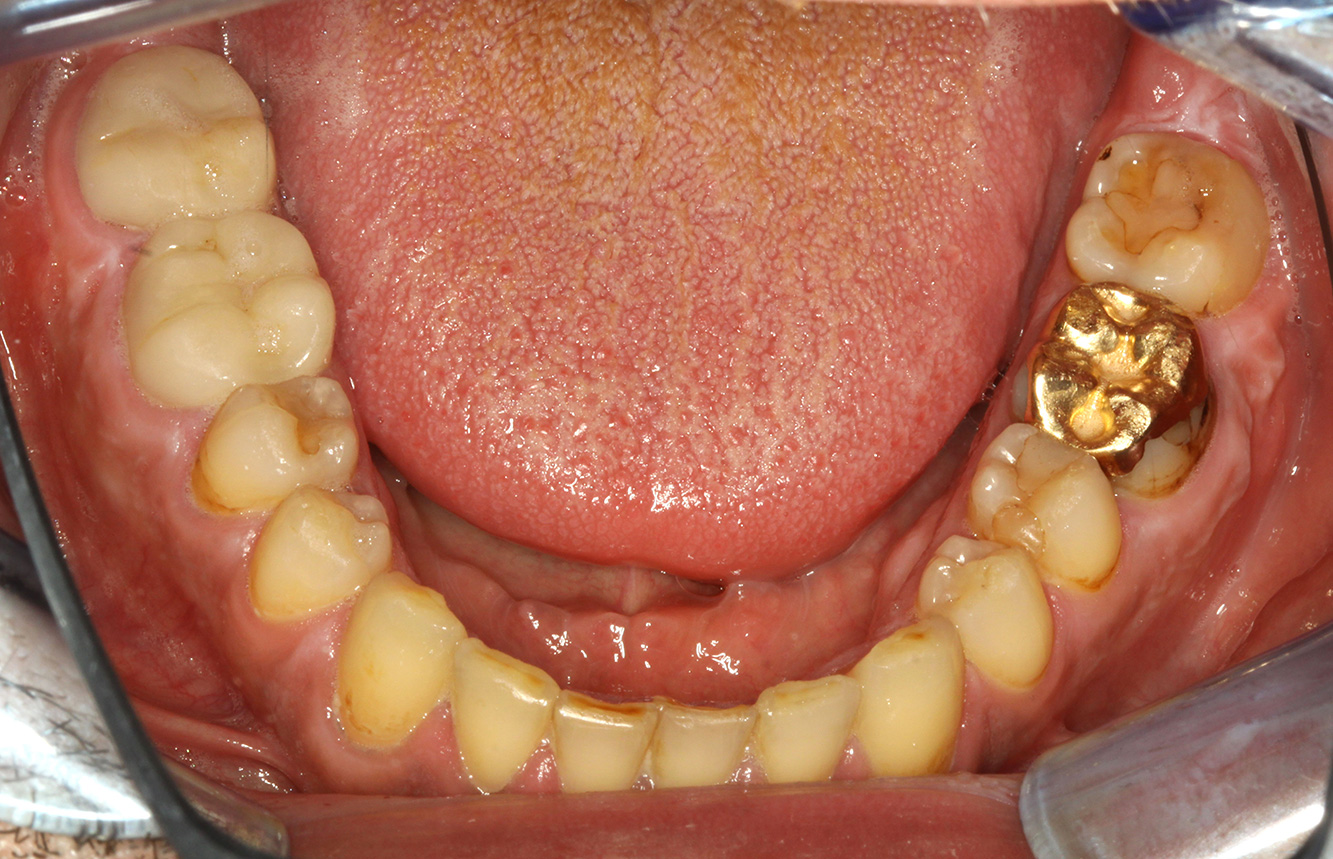

The endocarditis patient with active caries lesions*

The patient is 39 years old and has previously undergone aortic valve replacement due to valve failure and endocarditis. ASS 100 is taken regularly as an anticoagulant. In terms of lifestyle, the patient’s diet is classified as caries-promoting due to the regular consumption of sugary foods and the fact that six to seven meals are consumed daily. The patient’s oral health indicates a moderate risk of caries, with active lesions. The risk of periodontitis is low, but gingivitis is present. The following recommendations are made for prophylactic treatment.

No specific instrument recommendations can be determined for the prophylaxis session. Targeted application of air and rotary polishing can be used to gently reduce plaque and stains on the restoration edges, and to reduce recolonization niches for cariogenic bacteria (19).

Fluoridation is recommended to further support the prevention of caries, and especially to prevent new formation around the restoration edges, and to seal the root surfaces. Both of these measures can reduce the teeth’s sensitivity to temperature.

Due to the active caries lesions and the associated risk of progression, a shortened recall interval of three to four months is recommended.